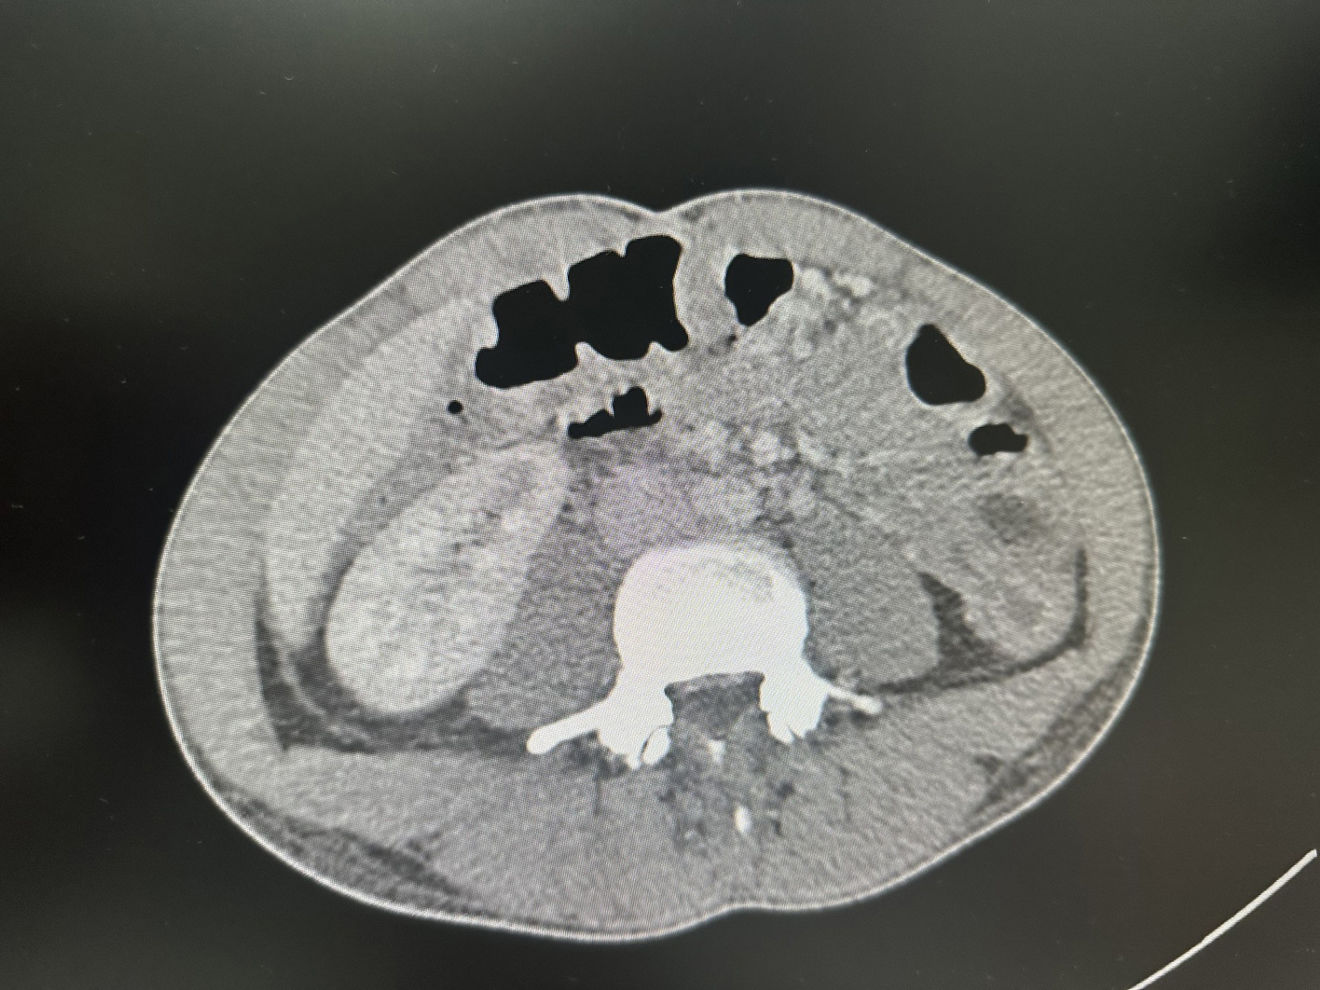

The abdominal ultrasound performed (Fig. 1) revealed the presence of inflammation of the wall of the large intestine (red arrow) with a thickness of 1.45cm (normal value, 0.3cm) and absence of peristalsis seen in the video, compared to the loop of the small intestine (blue arrow), which were findings consistent with colitis (later confirmed by CT scan [Fig. 2]).